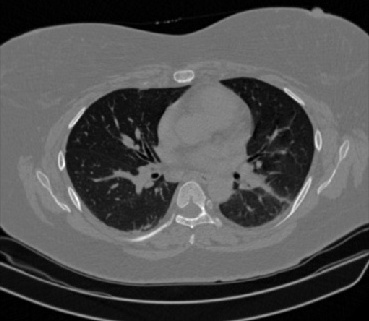

Figure 1 shows four CT scan slices, two from a non-COVID-19 CT scan, on the left and two from a COVID-19 scan, on the right. Bilateral ground glass regions are seen especially in lower lung lobes in the COVID-19 slices.